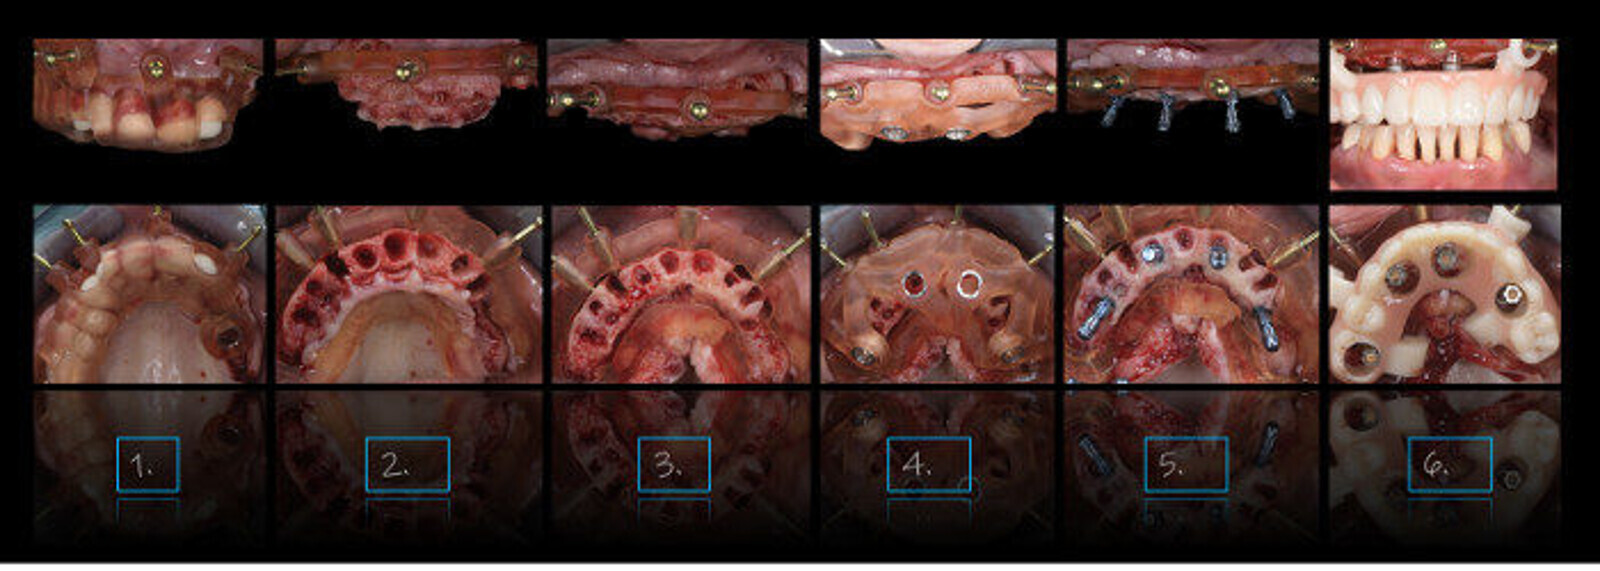

Cirurgia de arcada completa utilizando o sistema Smile in a Box. (Imagem: Ricardo Mitrani)

O conceito Smile in a Box tem vários atributos que podem aprimorar a experiência de tratamento do paciente. Ele permite que a equipe de tratamento analise e discuta as várias etapas que a terapia envolve em profundidade. Ele também garante que todas as peças e peças necessárias para realizar esses procedimentos sejam cuidadosamente selecionadas e solicitadas, incluindo uma restauração provisória gerada por CAD / CAM. Portanto, é uma adição bastante pragmática à nossa coleção interdisciplinar de recursos.

Acredito firmemente que melhorar a comunicação é possivelmente o aspecto mais importante da tecnologia digital na terapia com implantes. Permite-nos avaliar a visão da equipa de tratamento quando se trata de traçar os objetivos do tratamento, bem como da terapia sequencial de forma intuitiva, precisa e linear. Isso aumenta quando se trata de arcada completa, já que essa terapia normalmente não envolve apenas a colocação de implantes, mas muitas vezes também requer a redução óssea para garantir que o espaço protético adequado seja fornecido durante a cirurgia.